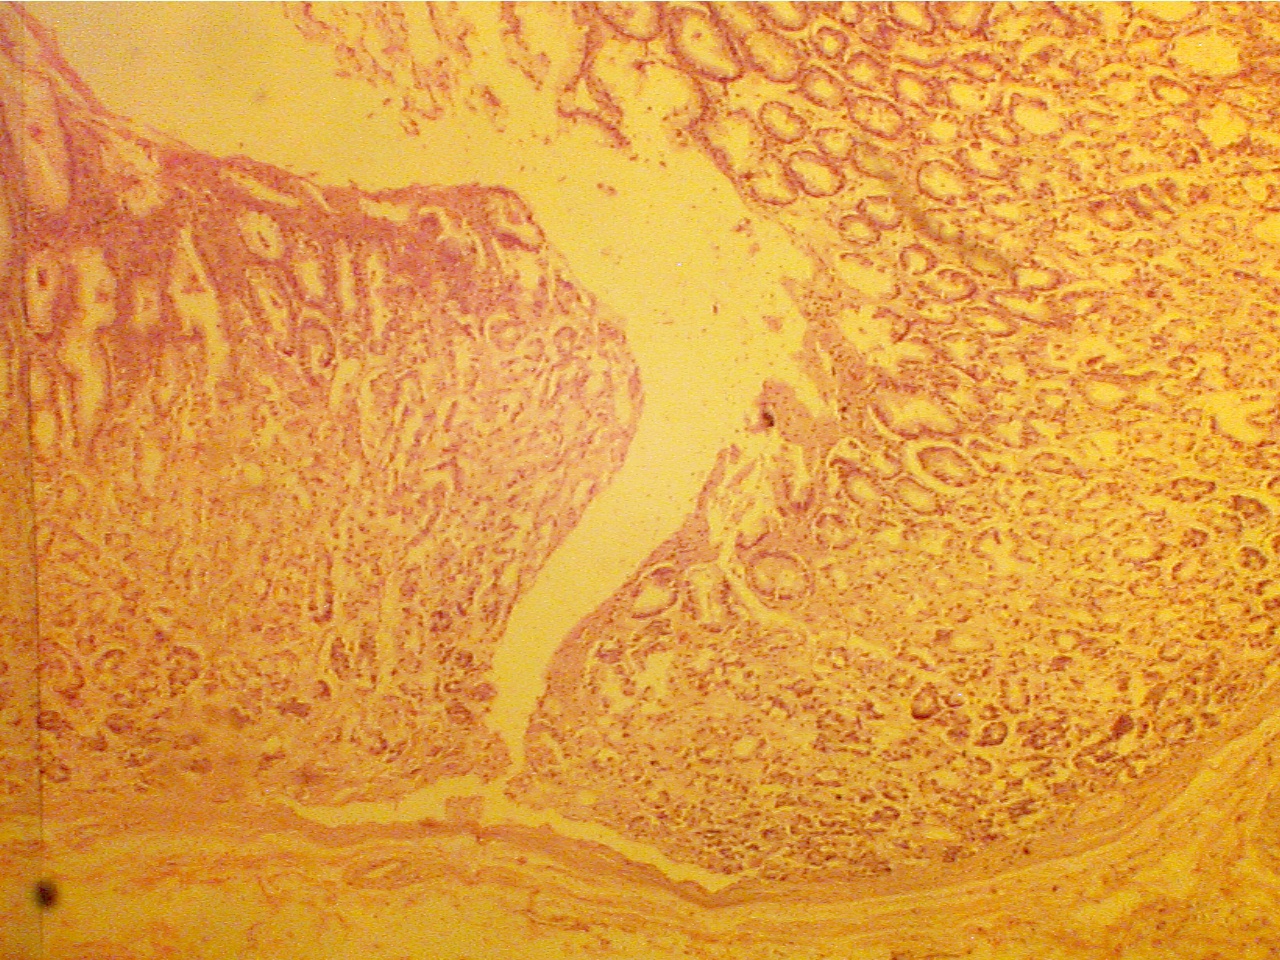

Notice that the inner lining of the stomach consists of a very thick mucosal layer consisting of tall rows of glandular cells running parallel to each other. The thick mucosa has a deep narrow gap extending to the bottom of the mucosa. This gap is the ulcer.

Normal stomach mucosa (40X2.8)                                                            Stomach mucosa with ulcer (40X2.0)